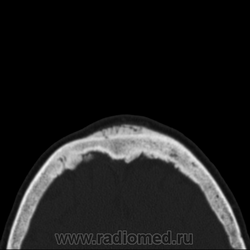

Какие аргументы будут? Ведь деструкции никакой нет. Изменения по типу реактивных. Просто анализирую для себя. Гиперостоз такой ни разу не стречал при такого рода сарком... Стенки пазухи клиновидной кости тоже изменены, утолщены. Коллеги, будут еще мнения?

Как насчет менингеомы, стелющийся вариант? Сочетание гиперостоза по внутренней и наружной пластинке черепа, реактивные изменения.... а можно dicom посмотреть?

Синдром Морганьи-Стюарта-Мореля - как вариант ограниченного гиперостоза лобной кости. Но там клиника просто вопиет))

При лобном гиперостозе изменения только по внутренней пластинке. Про менингеому можно почитать в книге Г.Ю.Коваль "Рентгенодиагностика заболеваний и повреждений черепа" (1984).

Вы правы, Марта, по внутренней, а здесь по обеим. Но мне кажется, что в любом случае это доброкачественное изменение...

Согласен, такие же мысли. Но такой "махровой" реакции ни разу не видел... Но то, что с двух сторон (оба кортикала) изменения - это, вероятнее, рекция на то, что в пазухе. А раз такие выраженные изменения, то, вероятно, процессу много лет. Итого - полипоз с периодическими обострения хронического синусита?

Значит так, Сергей Николаевич, представьте исследование корректно: с полной клиникой, рентгенограммами, подробной серией КТ. Пока это "рак, сифилис и несчастная любовь". Есть мягкотканная масса в пазухах и полости носа, есть ли деструкция стенок - по этим сканам судить нельзя. Есть спикулообразный периостоз в лобной кости, который м.б. при десятке заболеваний: от серповидноклеточной анемиии до остеосаркомы или мтс. Есть ли связь между этими изменениями - по тому, что вы показали - не видно.